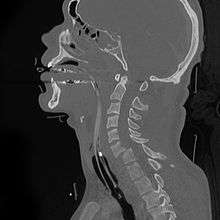

A fracture of the base of the dens (a part of C2) as seen on CT.